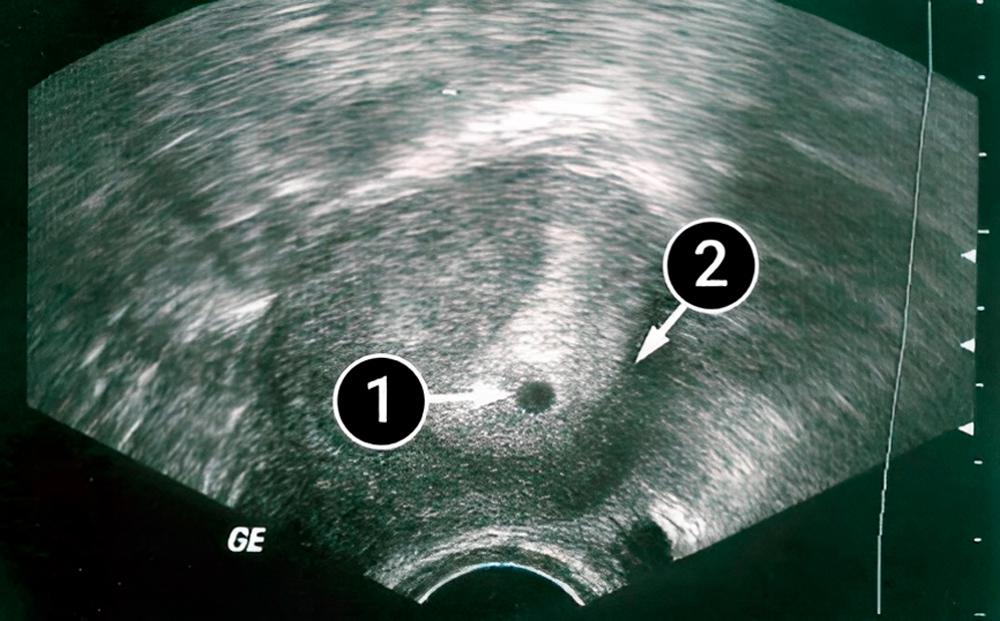

En el centro de la imagen, puede ver un pequeño punto oscuro que indica un embarazo con un único feto. Una gruesa capa de endometrio rodea fuertemente al saco fetal, y donde ésta se encuentra con la pared uterina, pronto comenzará a formarse la vasculatura y la placenta.

En la imagen, el útero tiene forma de pera. En ese momento, el útero aún no ha comenzado a crecer y a la madre aún no se le nota el embarazo.